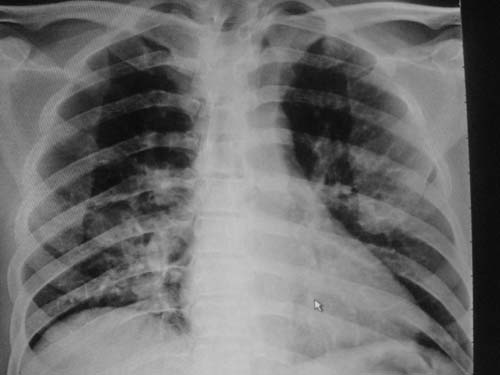

外伤病人,年龄忘了,中年人右侧肋骨骨折了,

这是刚住院拍的片子。